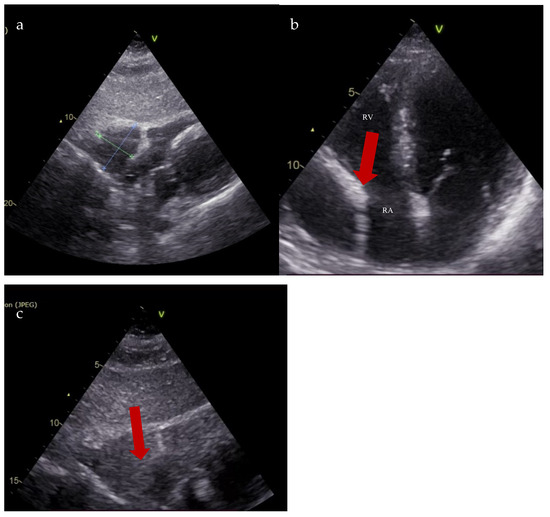

Follow-up transthoracic echocardiography revealed an enlargement of the previously noted structure, now measuring 36 × 49 mm, producing the systolic collapse of the right atrium. A saline contrast study confirmed the communication between the right atrium and the pericardial space (Figure 4).

Figure 4.

Transthoracic echocardiography. (a). Subcostal view: right atrial diverticulum 36 mm × 49 mm; (b). 4-chamber apical section: right atrial diverticulum with systolic collapse of the right atrium (red arrow); (c). Saline contrast test—subcostal section: communication between right atrial diverticulum and right atrium (red arrow) (RA—right atrium; RV—right ventricle).